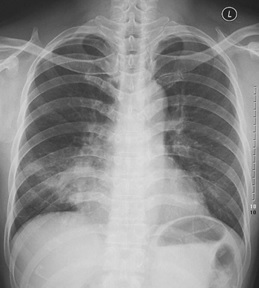

試題:根據(jù)下圖請做出正確診斷

A.正常心臟

B.心肌病(普大心)

C.風(fēng)濕性心臟病(梨型心)

D.主動脈型心(靴型心)